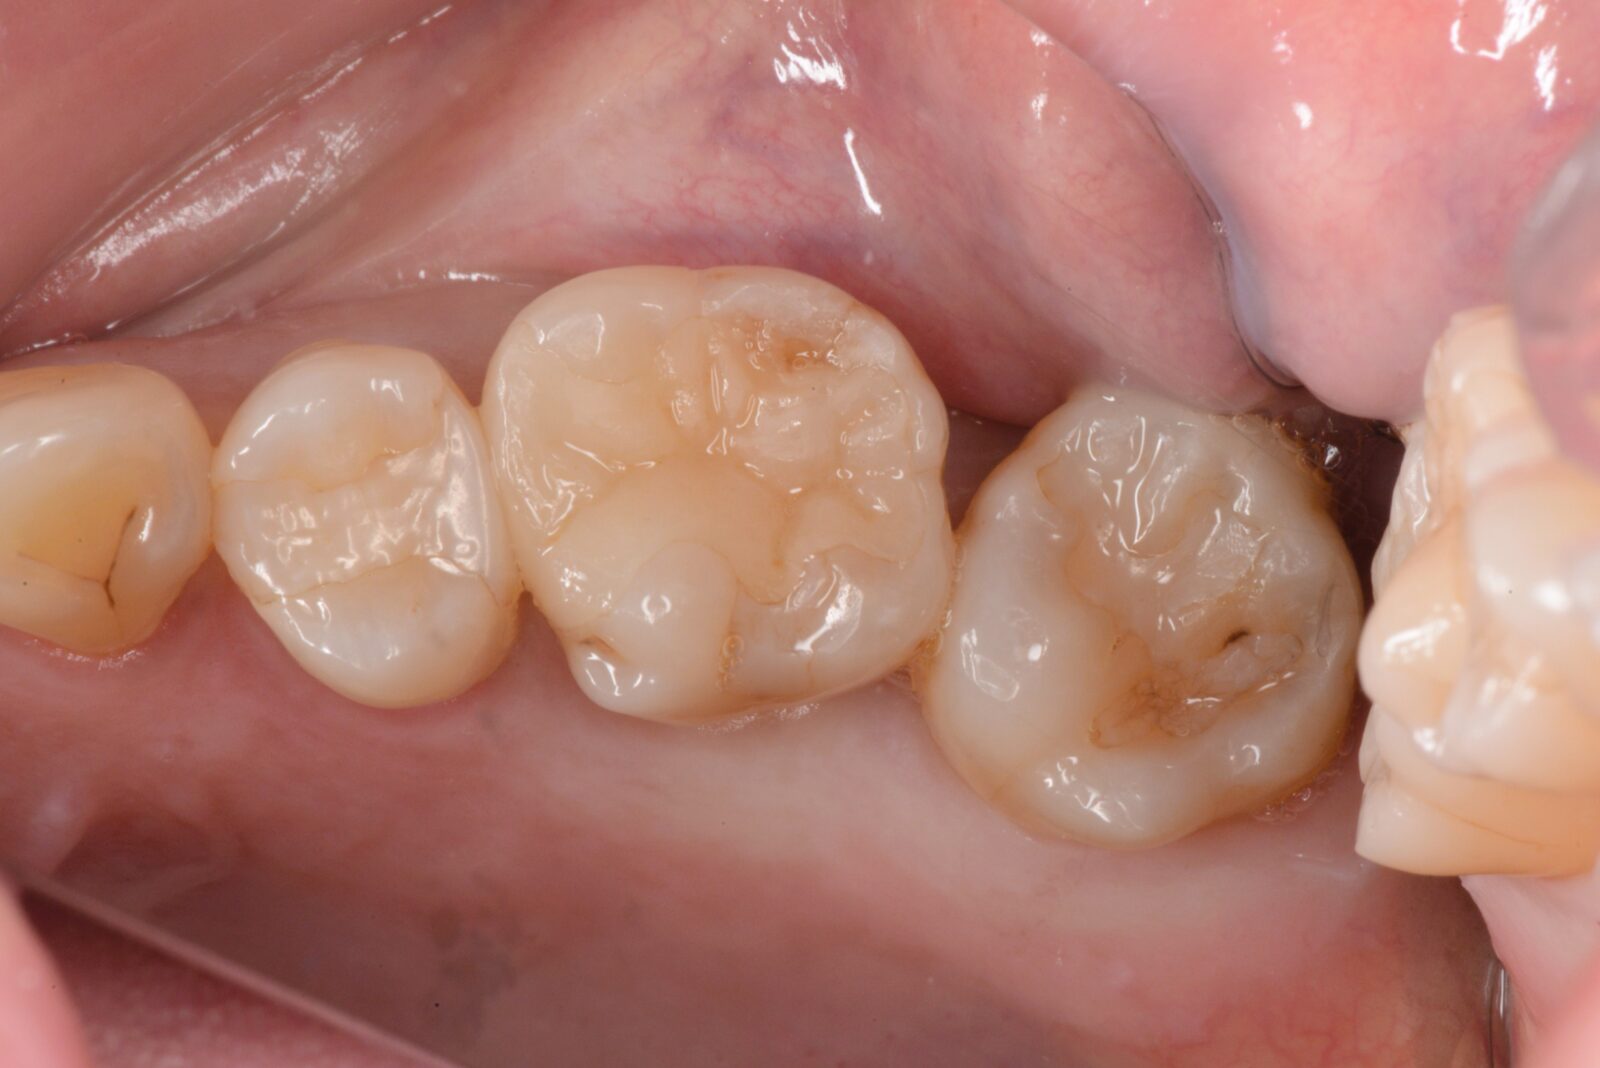

右上7ダイレクトボンディング

他の歯に続き不良修復物を治したいとのご希望。   旧充填物と感染歯質を除去し、表面のプラークを染め出し除去。   その後、エッチング・プライミング・ボンディング処理を行い、ファイバー繊維入りのコンポジットレジンを下地として敷き、その上に自費のコンポジットレ…